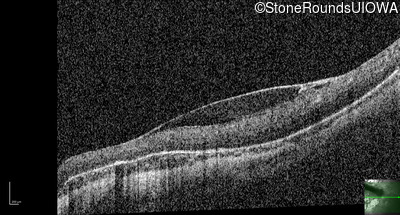

Optical Coherence Tomography - Right - 20/125

Exemplar